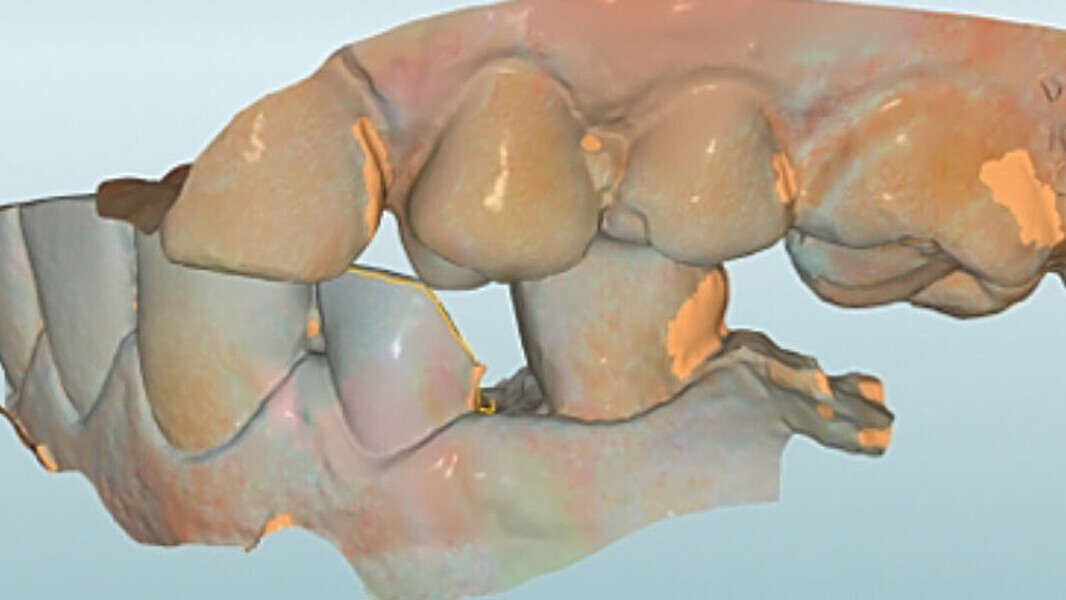

Fig. 5. Tras el escaneo intraoral se estableció el límite de la preparación.

Fig. 6. Mediante un escaneo vestibular se trasladó la intercuspidación habitual.